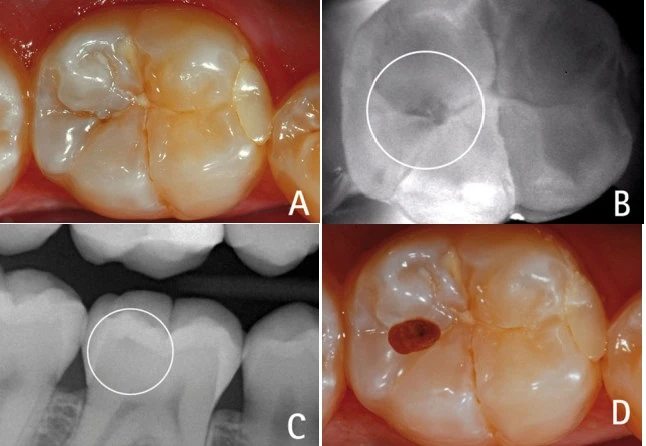

Hình 4: Vị trí tiếp giáp men-ngà (khoanh tròn) có sâu hay không sâu? Rất khó để nhận định trường hợp sâu mặt nhai mới đi qua lớp men răng chớm vào lớp ngà so với trường hợp không sâu răng nếu đánh giá trên phim X-quang tại chỗ.

Hiệu ứng mach band trong X-quang

nha khoa là ảo ảnh thị giác gây ra một vùng thấu quang giả nằm giữa hai cấu trúc có mật độ quang học khác nhau (gây ra mức độ cản quang khác nhau), ví dụ như men răng và ngà răng. Một đường mỏng nhìn thấy được ở bề mặt ngà răng và sâu răng có thể nhầm lẫn với nhau. Hiện tượng Mach band thông thường chỉ giới hạn là một đường mảnh 0.5mm dưới đường nối men-ngà (4).

Có thể thấy điều này rõ ràng hơn ở ranh giới giữa vật liệu phục hình (đặc biệt có chứa kim loại) nằm giữa men và ngà răng. Hiệu ứng này thường gây chẩn đoán sai thành sâu răng thứ phát hoặc làm nha sĩ đánh giá sai về độ lớn của tổn thương sâu răng. Nó cũng gây chẩn đoán thiếu trong trường hợp gãy chân răng theo chiều ngang do sự khác biệt về cường độ tia (radiographic intensities) của răng và xương. (5)

Cách khắc phục (theo ý kiến cá nhân của tôi)

– Kết hợp với triệu chứng lâm sàng khác. Mach band có thể gây nhầm lẫn là một sâu răng mặt nhai tới lớp ngà. Trên lâm sàng cần làm sạch các hố rãnh nghi ngờ đối với xoang I. Trên X-quang tìm các đường thấu quang hình tam giác ở phần men răng mặt bên là đường vào cho các sâu xoang II có thể lan ra làm sâu ngà tiếp giáp men răng gây nhầm lẫn.

– Với các chẩn đoán gãy chân răng, phối hợp với lâm sàng đánh giá độ lung lay và tiền sử chấn thương/đau. Có thể kết hợp với các phim 3D khác.

– Kết hợp với các chẩn đoán hiện đại khác: ví dụ Diagnodent có thể cho biết mức độ lan của sâu răng bên dưới khi bên trên còn lớp men phủ mà đường vào rất nhỏ, đặc biệt với những trường hợp sâu lan từ rãnh mặt ngoài hoặc mặt trong trên phim X-quang không thể thấy được.

Hình 5: Một lỗ sâu nhỏ trên mặt nhai (A) có thể bị bỏ qua không xử lý nếu chỉ khám bằng mắt thường hoặc với phim X-quang (C). Với sự trợ giúp của Diagnodent có thể thấy sâu răng bên dưới phần men hơi đổi màu (B). Sau khi mở lỗ sâu (D).